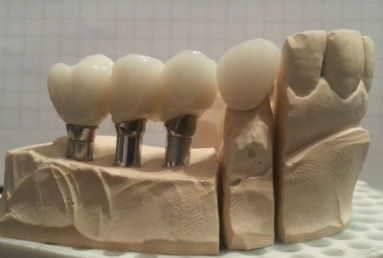

After the osseointegration of the implants three porcelain and zirconium crowns were made. At the same time full ceramic crowns were made for the left canine and the two right premolars, which had deep cavities and needed root canal treatment.